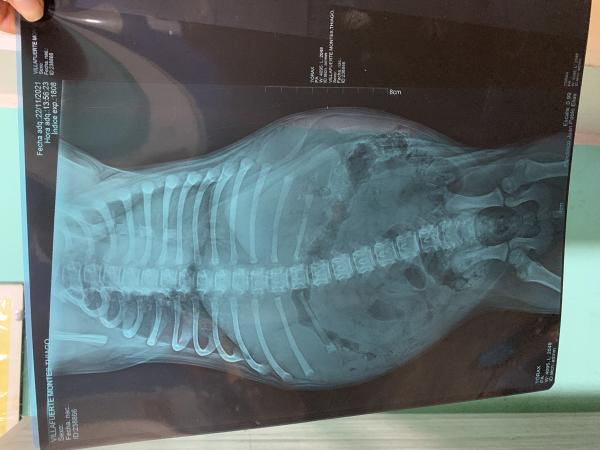

Hola quisiera que de su opinión sobre mi perro de 2 meses, el siempre ha orinado mucho, pero ahora ha estado mal y empecé a contar cuantas veces hace pipí, en dos horas hace al rededor de 8 veces. Le adjunto las placas que le sacaron porque también tenía las amígdalas inflamadas, su pecho le suena, el veterinario al que le lleve dijo que era tos de perrera, estuvo con antibióticos con aguja 3 días y 6 con pastillas aún así no mejoro el sonido de su pecho pero si bajo sus amígdalas. Quisiera su opinión al respecto.